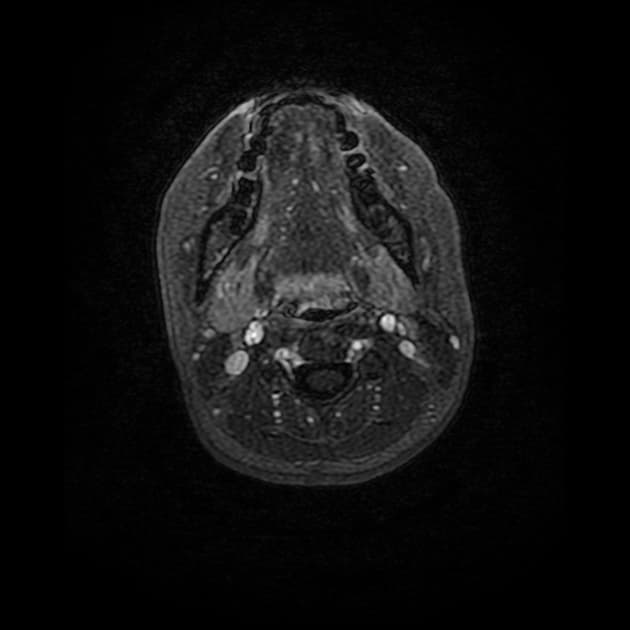

Có tăng tín hiệu nội tủy sống trên các dãy xung T2 và STIR, chủ yếu ảnh hưởng đến chất xám trung tâm, từ mức T8-T9 xuống đến tận tủy hình nón (conus medullaris). Ở một số đoạn, tín hiệu bất thường nội tủy có dạng "owl's eye appearance" (dấu hiệu mắt cú).

Tình cờ phát hiện tràn dịch màng phổi (pleural effusion) hai bên và các tín hiệu bất thường ở phổi, có thể là đông đặc (consolidation) và/hoặc xẹp phổi (atelectasis).

Thiếu máu cục bộ tủy sống (spinal cord ischaemia) – phù hợp với biến chứng của bóc tách động mạch chủ (aortic dissection).